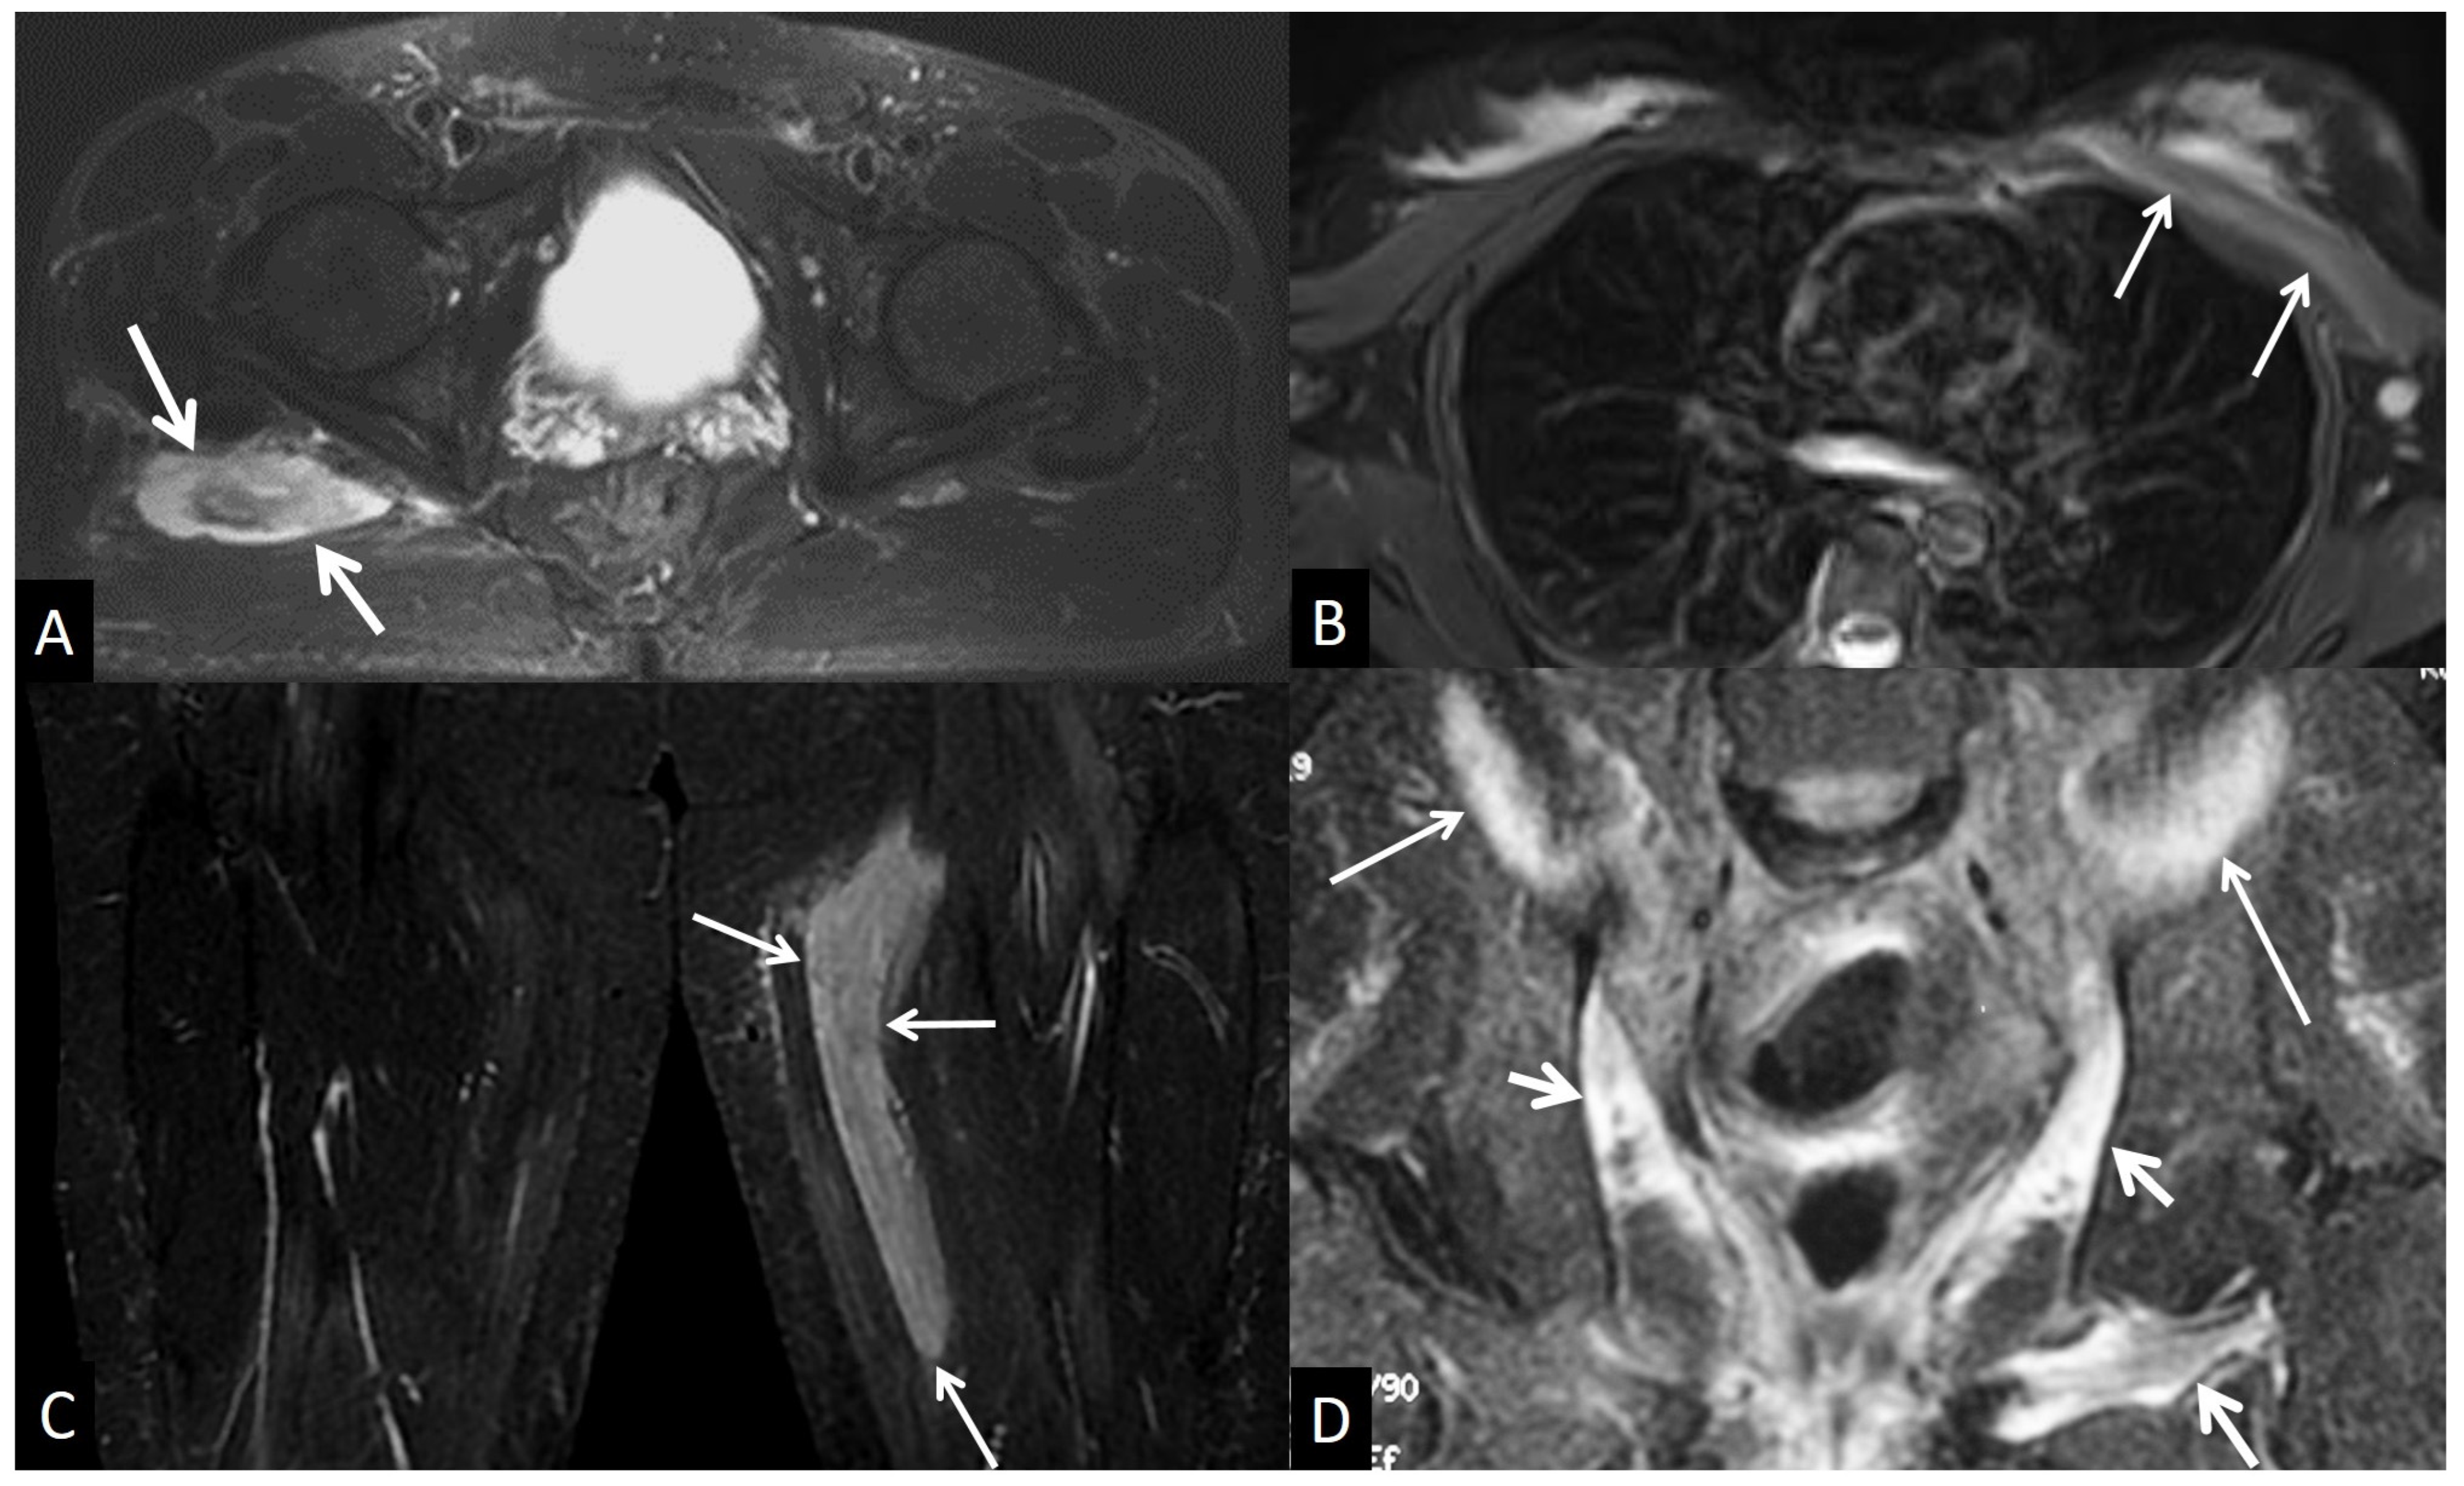

5. Muscles and Soft Tissues

5.4.4. Rhabdomyolysis

5.4.5. Myositis Ossificans

5.5. Neoplasm and Post-Therapy Soft-Tissue Changes

5.5.1. Neoplasms